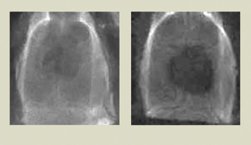

Hubbell and his coworkers tested their scaffolding on rats from which they’d removed small circular sections of skull. Disks made of the scaffold material stimulated bone regeneration as well as cow collagen does.